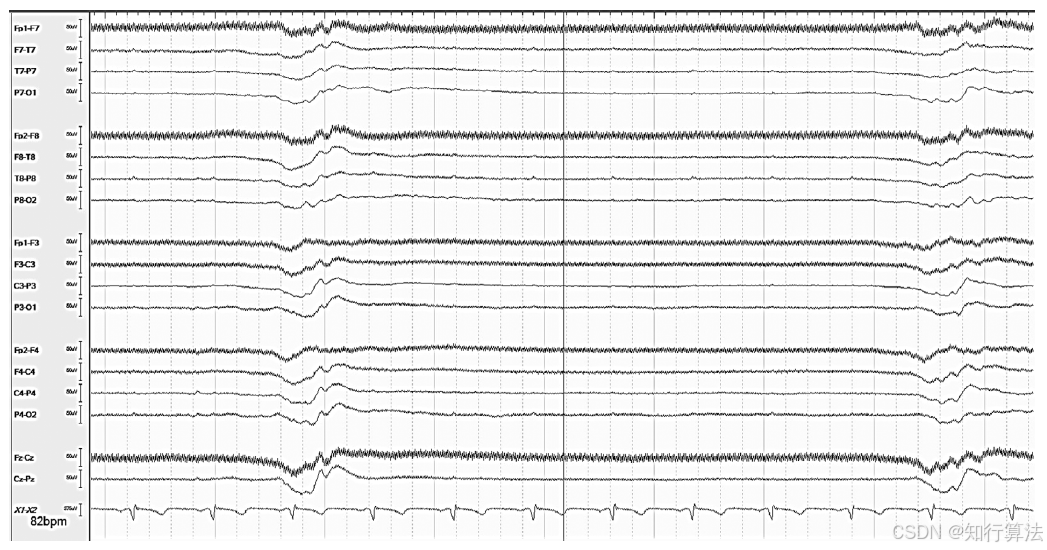

波形特征:规则、慢节律(单发或爆发),常累及前头部,位置不定。频率与呼吸机设定频率一致(图4:每6秒一次,对应呼吸频率10次/分)。

图4:每 6 秒一次的呼吸机周期性伪差